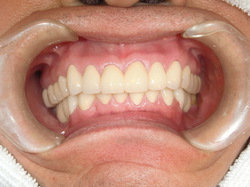

2016年6月にサイナスリフトをおこなった症例(30…

ストレスマネージメントとしての睡眠時のはぎしりは時として、咬合の崩壊をもたらします。 30代であれば、奥歯の再生とスムーズな歯ぎしりの誘導は、精神的にも全身の健康にも及ぼす効果は計り知れません。それほど奥歯の再生は重要です。 上あごの骨が無いところにインプラントを埋入しなければなりません。とる…